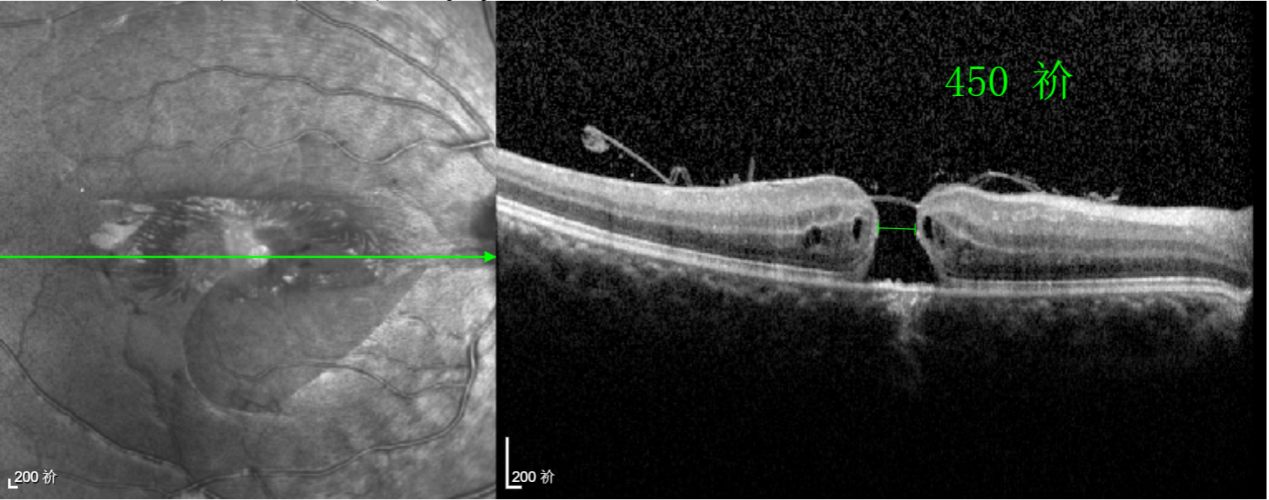

經(jīng)過詳細的檢查和評估,王曉波主任決定采用“內(nèi)界膜翻轉(zhuǎn)覆蓋聯(lián)合粘彈劑固定術(shù)”為誠誠進行治療。

除此之外,利用自體組織覆蓋為黃斑裂孔提供了理想的愈合環(huán)境,裂孔閉合速度顯著快于傳統(tǒng)方法。誠誠接受手術(shù)24小時后,檢查可見內(nèi)界膜瓣位置良好;術(shù)后1個月,黃斑裂孔已經(jīng)閉合,視力恢復(fù)到0.5;術(shù)后兩個月,視力進一步提升到0.7。